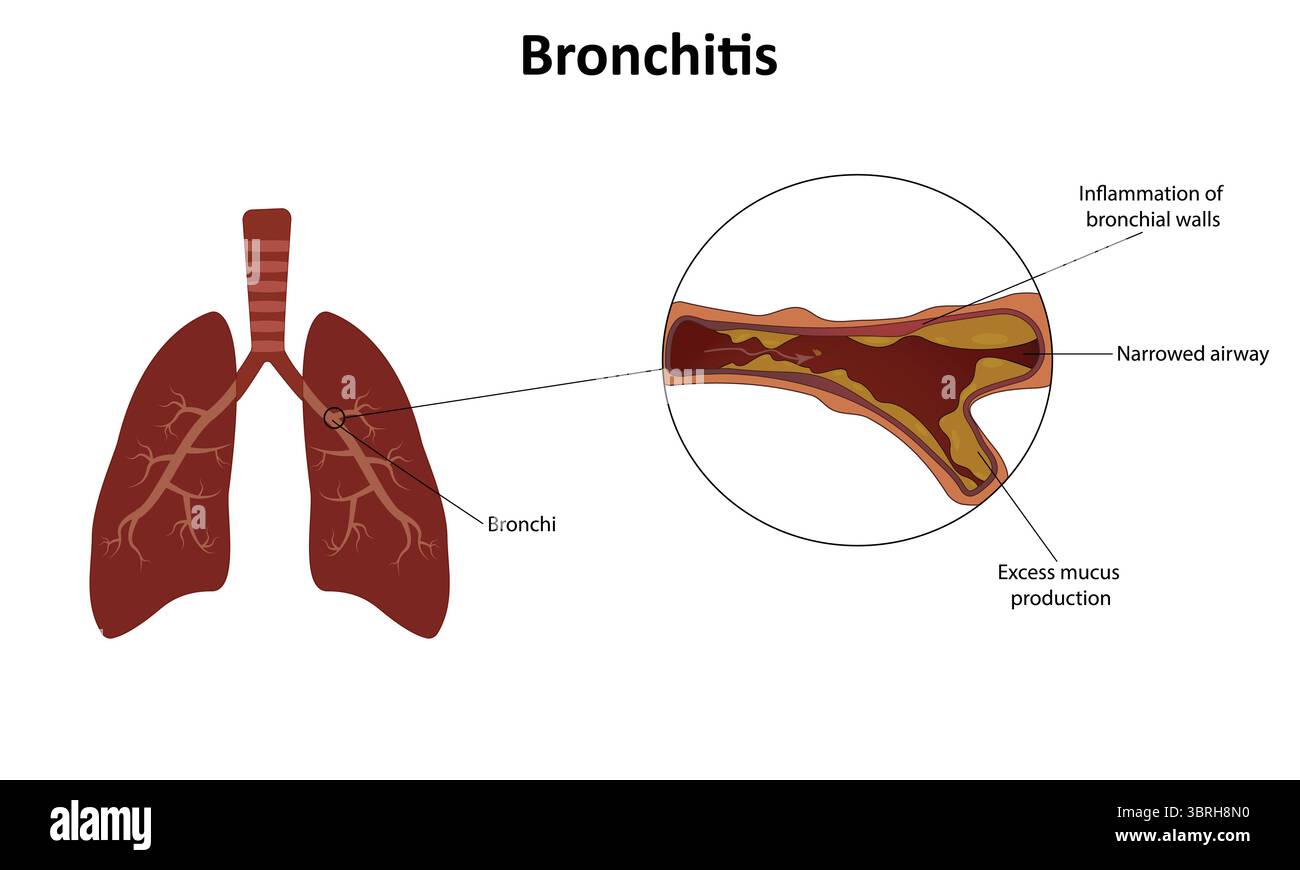

Bronchitis vector illustration Stock Vectorhttps://www.alamy.com/image-license-details/?v=1https://www.alamy.com/bronchitis-vector-illustration-image685721484.html

Bronchitis vector illustration Stock Vectorhttps://www.alamy.com/image-license-details/?v=1https://www.alamy.com/bronchitis-vector-illustration-image685721484.htmlRF3BRH8N0–Bronchitis vector illustration